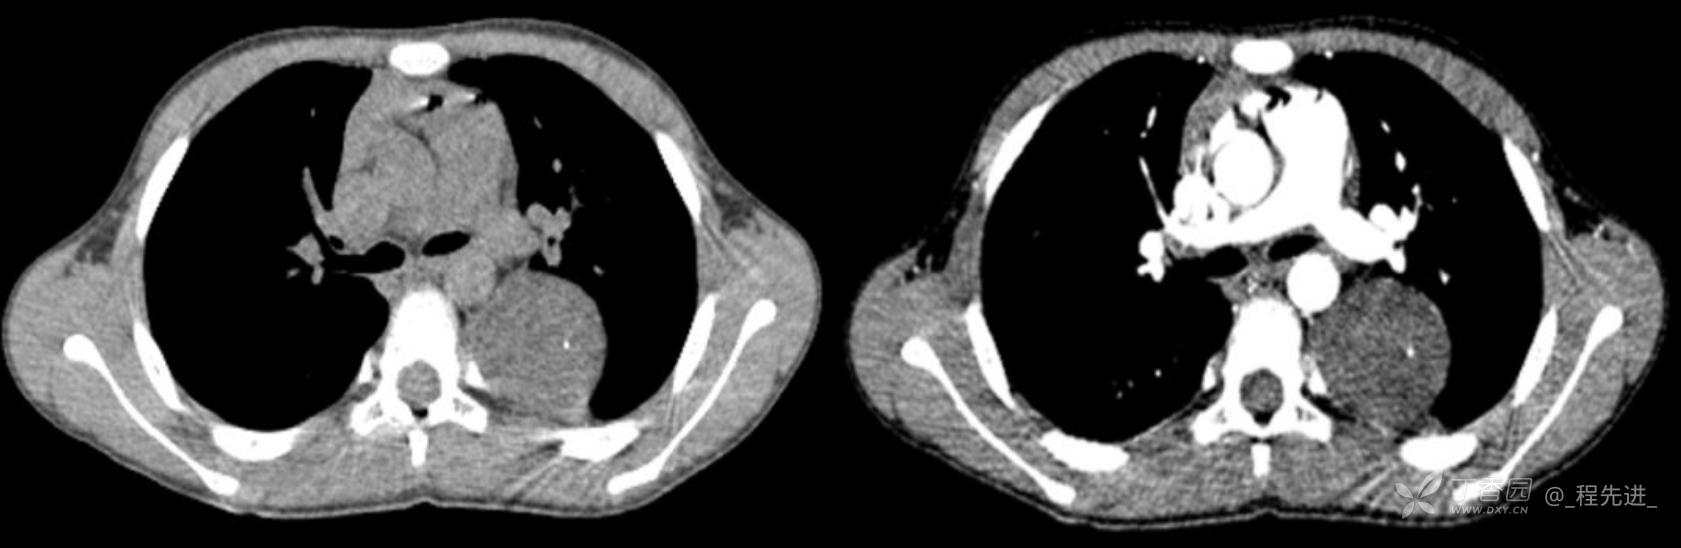

11月特别精彩病例|胸片示“左侧胸腔包裹性积液”,CT增强你诊断啥?【病理已公布】

呱呱叫了 等 3 位达人已点赞男,11岁,患儿因其爷爷近期在我院诊断“肺结核”,于外院行结核筛查,胸片示“左侧胸腔包裹性积液”,近期无咳嗽、发热、纳差、盗汗、乏力、胸痛、胸闷、气促不适,精神反应可,为求明确“左侧胸腔包裹性积液”病因,遂来我院门诊就诊,门诊以“胸腔积液查因”收住入院。发病以来,精神尚可食欲如常,大便如常,小便量如常,体重无明显变化